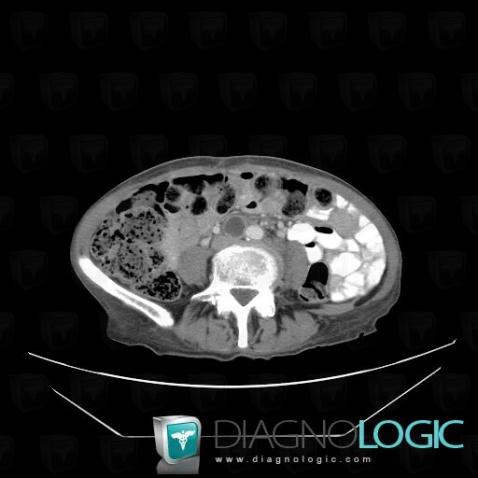

Voici les informations spécifiques à l'image clé ci dessus:

- Diagnostic Métastase (lié à Adénopathie), Localisation(s) Rétroperitoine, comportant les gammes Masse rétropéritonéale kystique

- Diagnostic Métastase, Localisation(s) Rétroperitoine, comportant les gammes Masse rétropéritonéale hypodense, Adénopathie rétropéritonéale